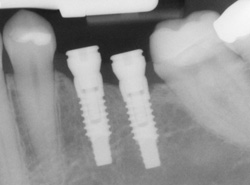

What is a dental implant?

An excellent option for replacing missing teeth is a dental implant. The most common type of dental implant is the root-form implant which, as its name implies, is about the same size and shape as the root of a tooth. Root-form implants are made from titanium, and they are surgically placed in the jawbone where they heal firmly in place. After healing is complete, a crown or other dental restoration can be placed on the implant.